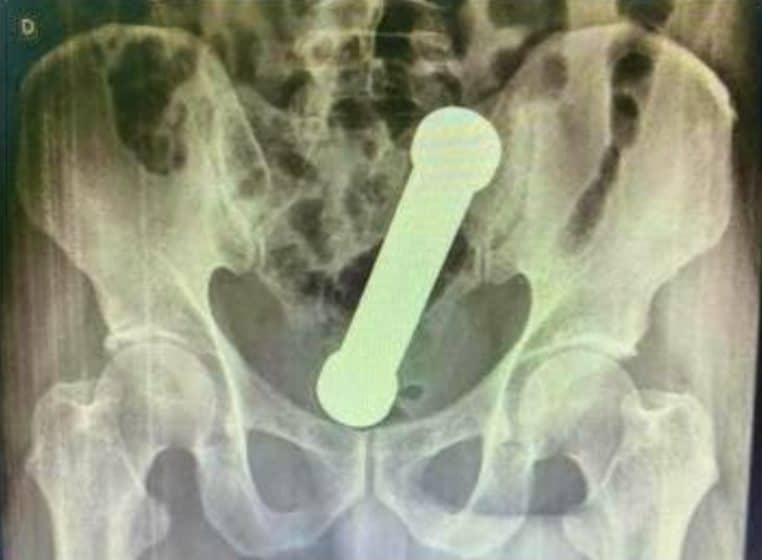

Avec sa forme phallique, l’objet de musculation mesure 20 centimètres de long et environ 5 centimètres de large. L’homme a certainement réussi à se faire beaucoup de bien avec l’haltère, mais son bonheur a vite été gâché.

Maux de ventre, nausées et impossibilité d’aller sur le trône

Le Brésilien a donc attendu deux jours avant de se rendre à l’hôpital. Et il n’a pas eu d’autres choix lorsqu’il a été pris de maux de ventre, de nausées et d’une impossibilité à se rendre sur le trône. Et à l’hôpital, les médecins n’en reviennent pas. Après une radio, ils ont découvert l’haltère de deux kilos au chaud dans le derrière de l’homme.

Honteux et peut-être gêné, l’homme est peu coopératif avec les médecins. Lorsque ces derniers découvrent l’haltère dans les fesses du patient, ils le mettent sous sédatif afin d’extraire l’objet avec une pince chirurgicale, comme le rapporte 20 Minutes. Mais cela ne suffit pas, et l’haltère est toujours dans son derrière. Alors les médecins doivent utiliser la manière forte… Et une main ferme.

En effet, l’homme a dû subir une « extraction manuelle » de l’haltère. Le médecin a dû introduire son bras dans les fesses du patient pour parvenir à extraire l’objet. Selon le Journal of Surgery Case Reports, les hommes sont nombreux à s’insérer des choses dans les fesses. Selon le journal, la plupart des patients ayant quelque chose dans le derrière sont les hommes entre 20 et 40 ans.